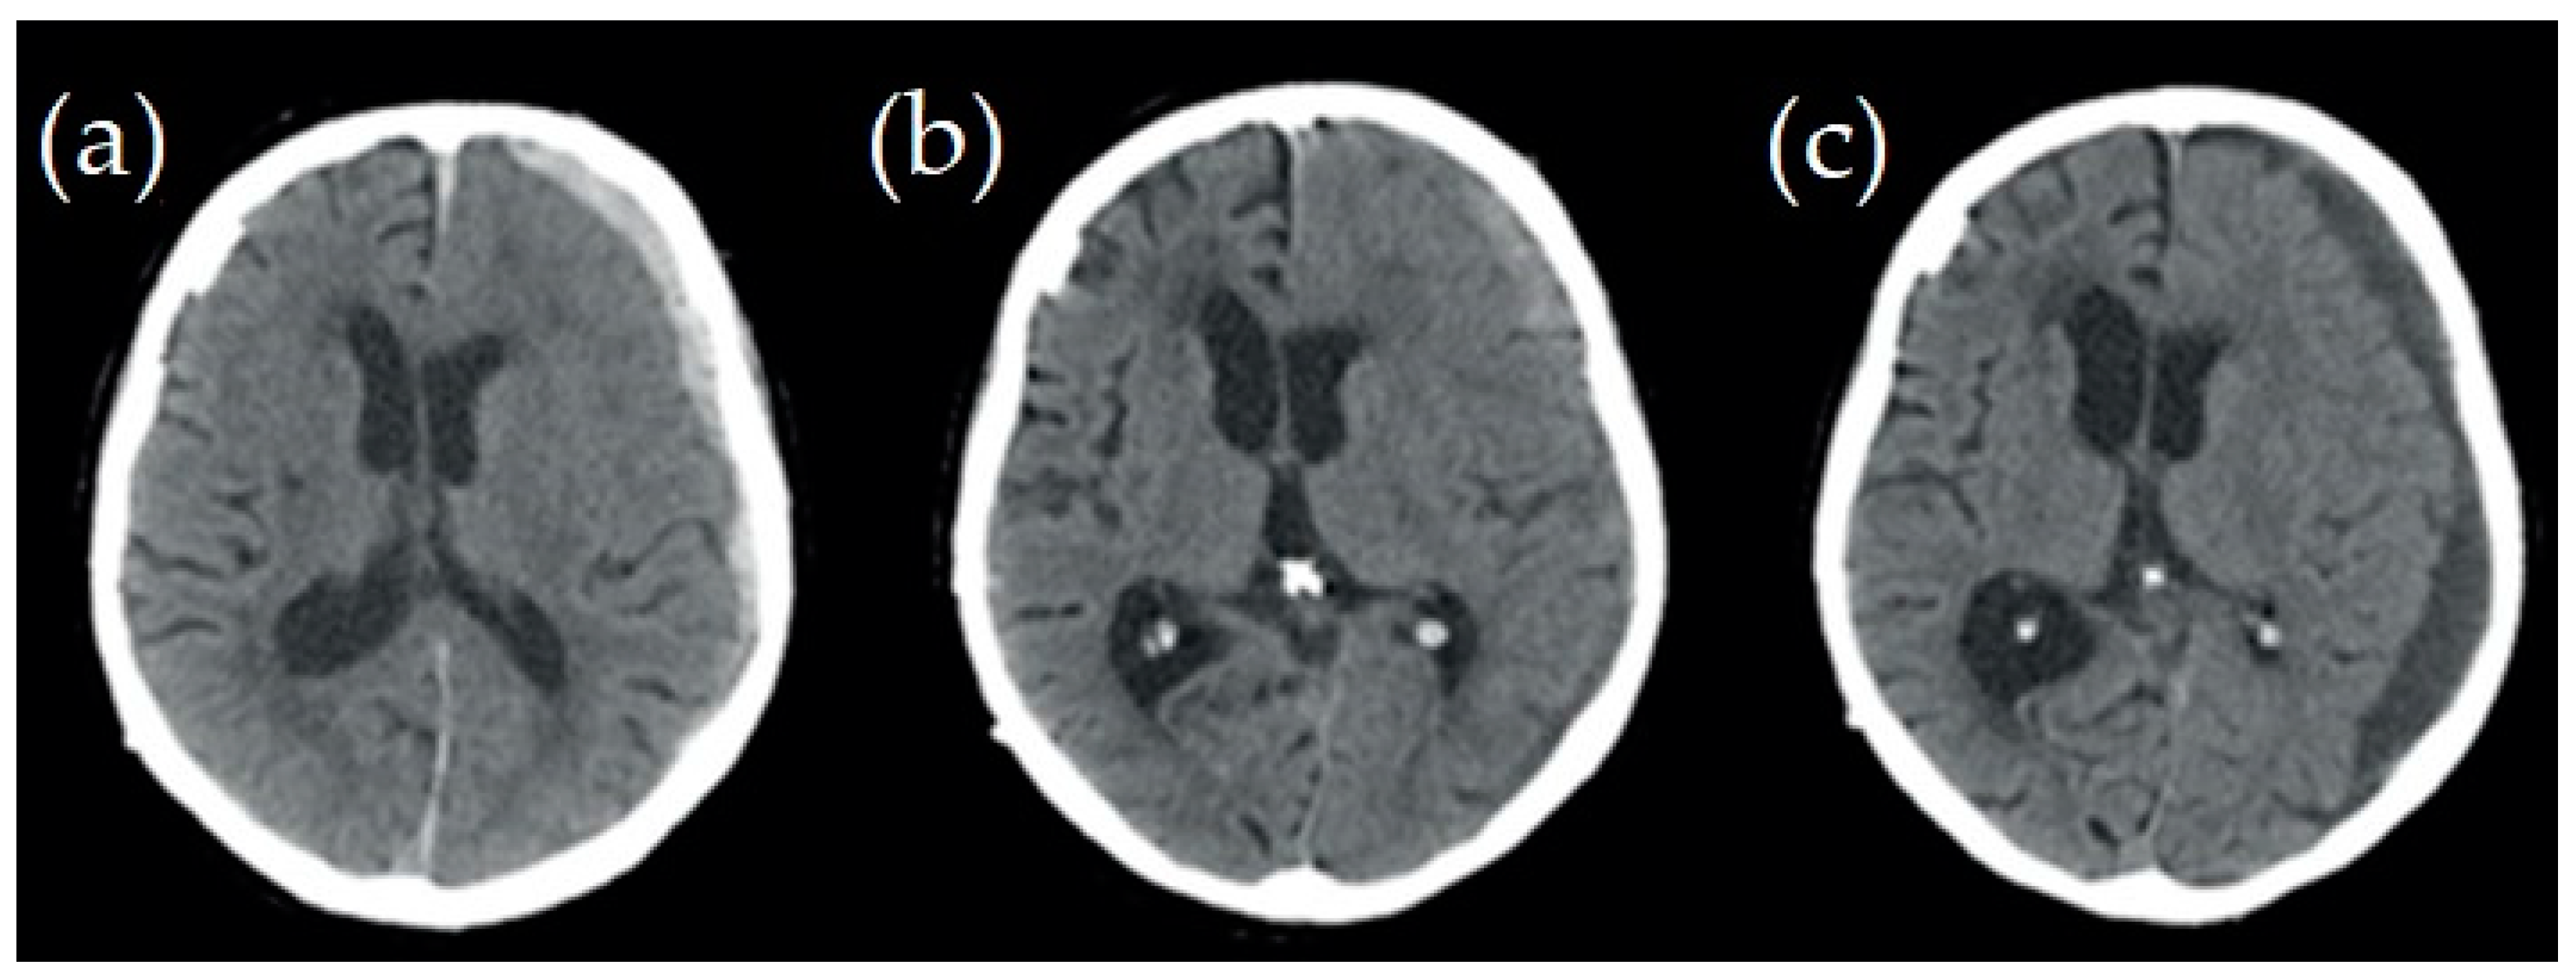

- Tsui, E.Y.K.; Fai Ma, K.; Cheung, Y.K.; Chan, J.H.M.; Yuen, M.K. Rapid Spontaneous Resolution and Redistribution of Acute Subdural Hematoma in a Patient with Chronic Alcoholism: A Case Report. Eur. J. Radiol. 2000, 36, 53–57. [Google Scholar] [CrossRef] [PubMed]

- Kim, H.I.; Oh, Y.J.; Cho, Y.N.; Choi, Y.-C. Subdural Hemorrhage Mimicking Peripheral Neuropathy. J. Korean Neurosurg. Soc. 2014, 56, 166–167. [Google Scholar] [CrossRef] [PubMed]